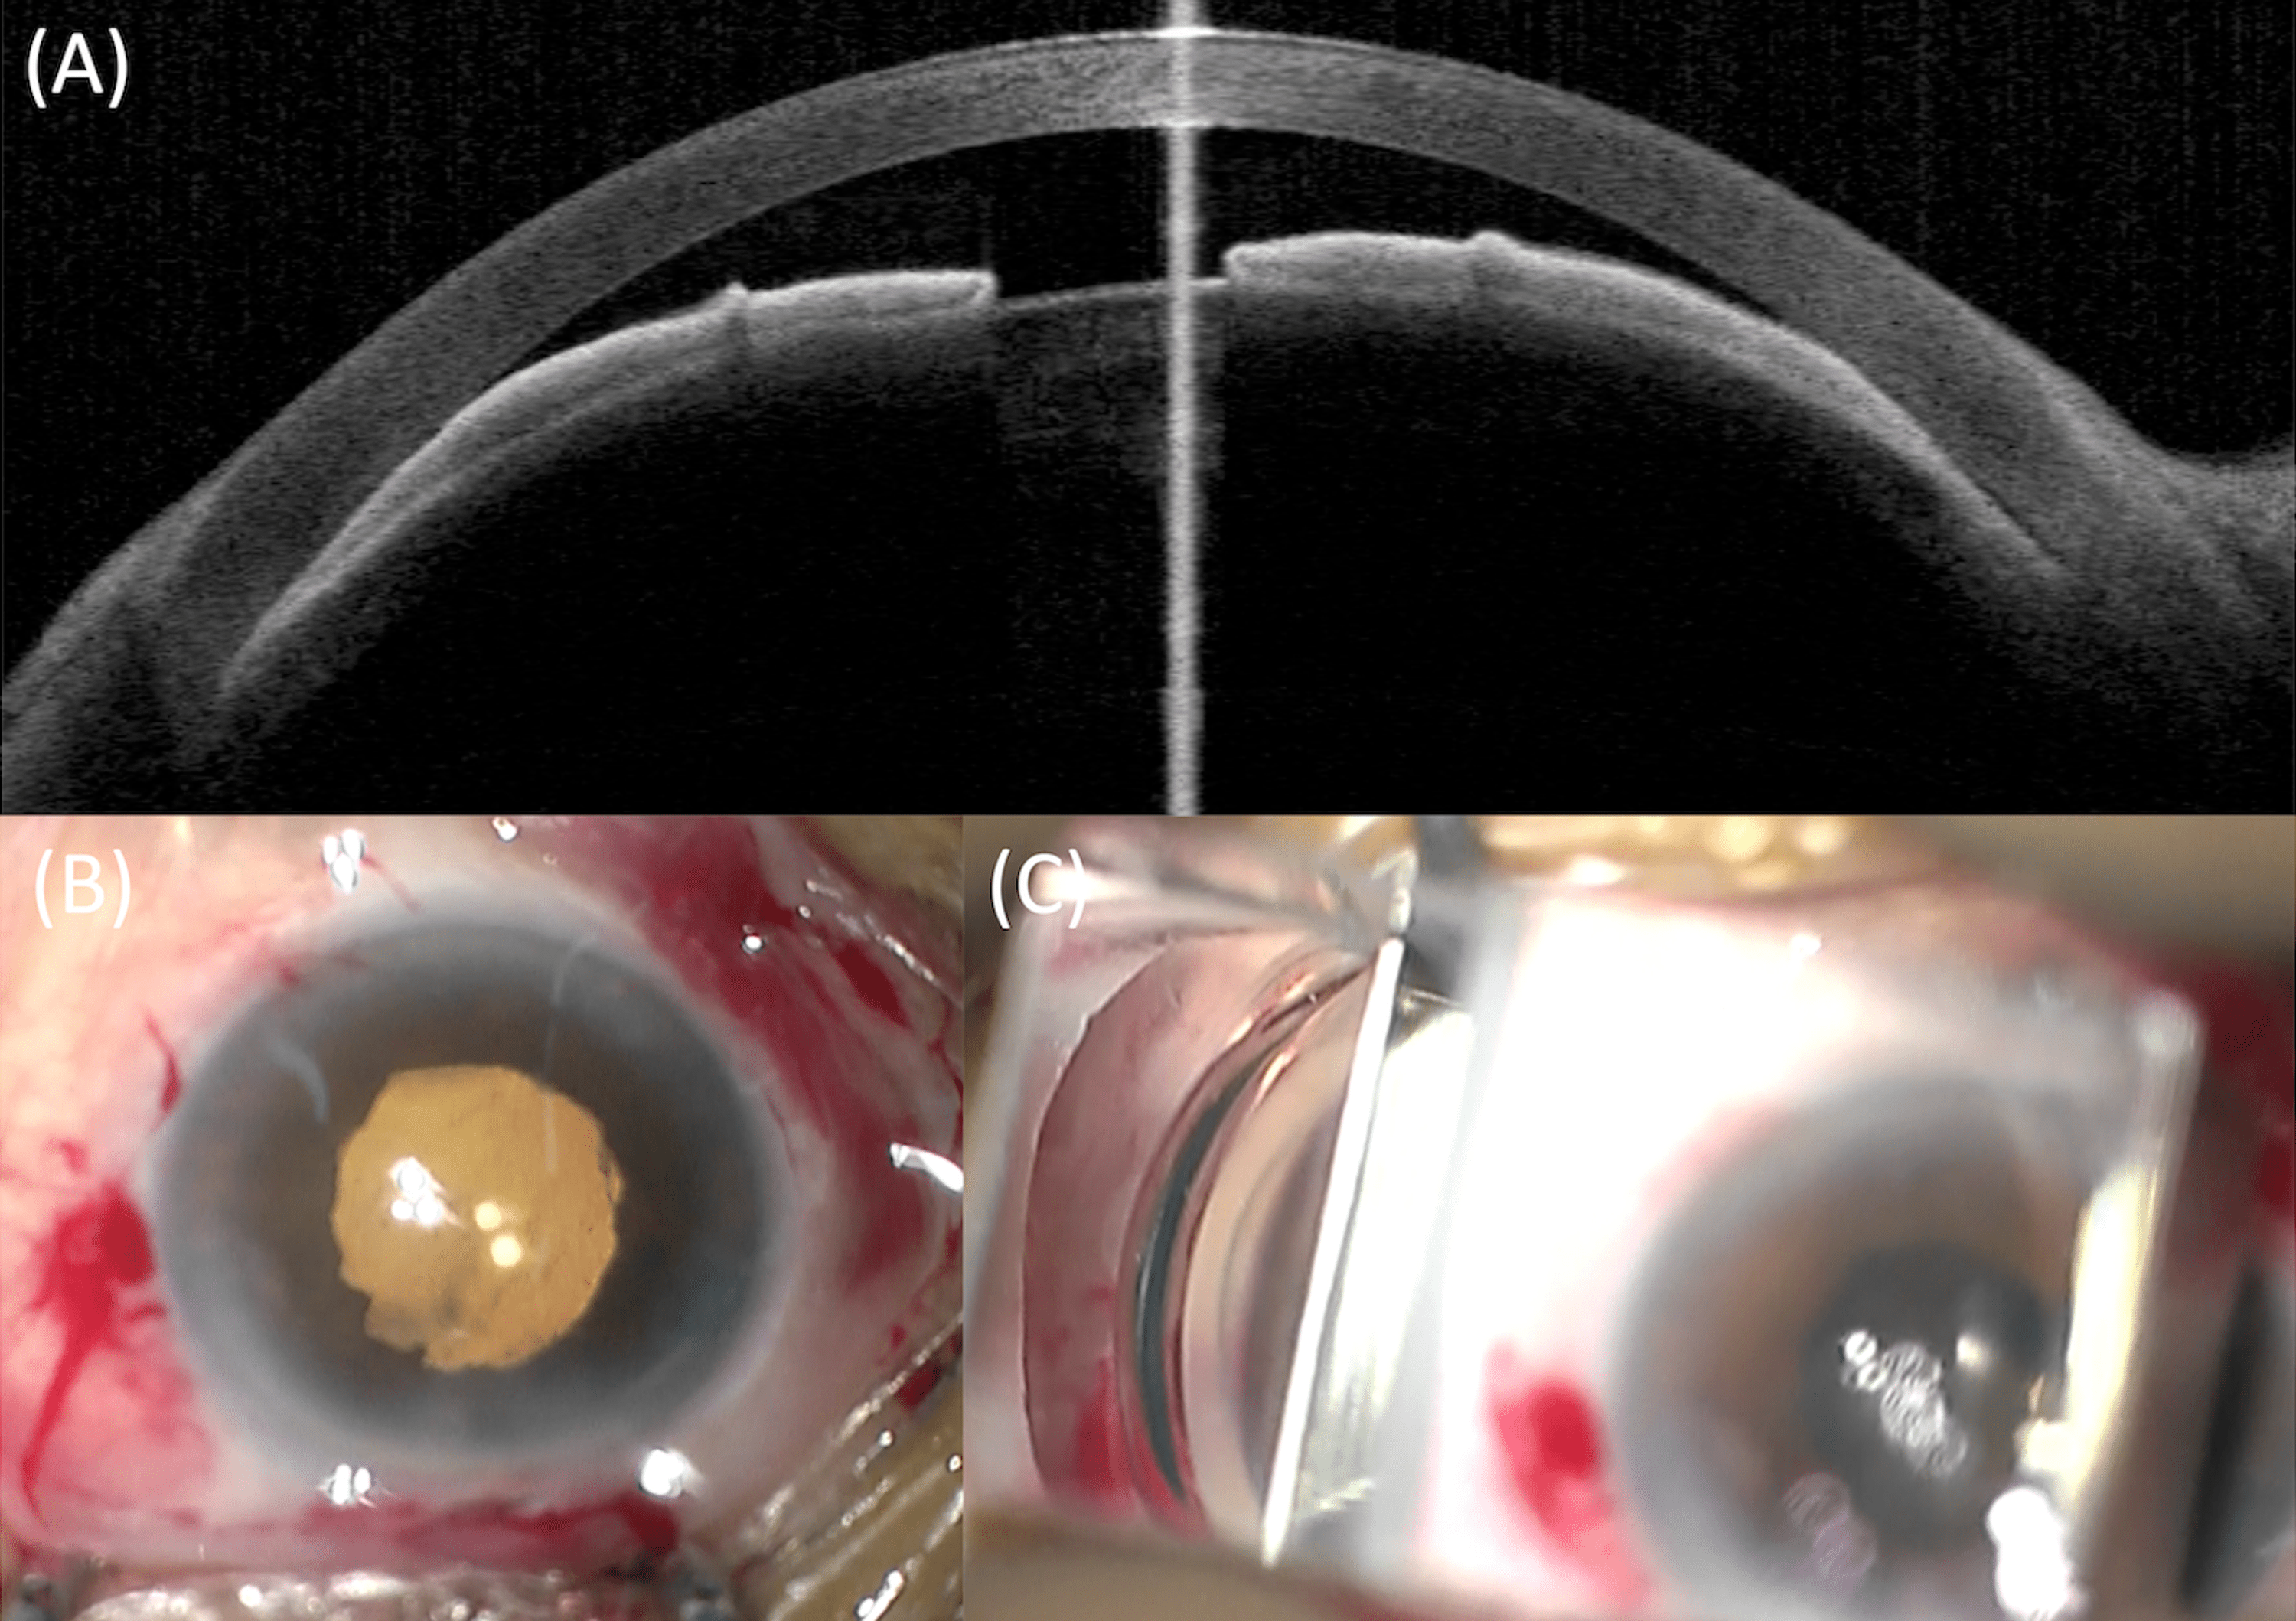

Malignant After Immediate Primary Phacoemulsification for Acute Primary Angle Closure Lens Replacement Surgery For Acute Angle Glaucoma During the procedure, your eye surgeon will open up your. The use of cle as a primary treatment option has been tested against lpi in the eagle study, a large rct that enroled. Lens replacement surgery can benefit patients with acute angle glaucoma by improving vision and reducing the risk of future. Removal of the lens may reduce the risk. Lens Replacement Surgery For Acute Angle Glaucoma.